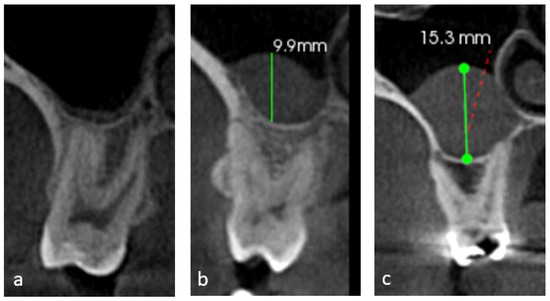

| The relation of roots of posterior maxillary teeth to the sinus floor (RPMT) | Type 0 | 583 | 45.9 |

| Type 1 | 403 | 31.8 | |

| Type 2 | 183 | 14.4 | |

| Type 3 | 77 | 6.1 | |

| Type 4 | 23 | 1.8 | |